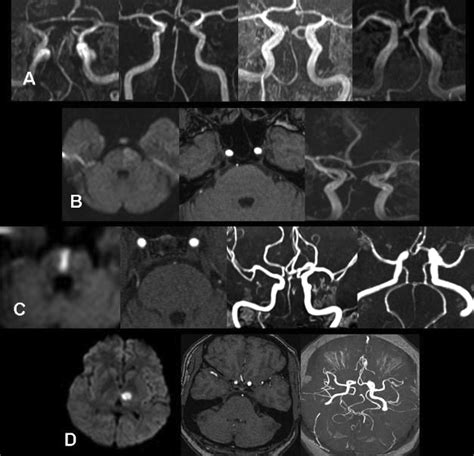

Diagnosis and Emergency Imaging

When a patient arrives at the emergency department with suspected neurological deficits, medical professionals follow a strict protocol. Speed is the priority. Doctors will typically perform a neurological exam and immediately order imaging studies to differentiate between an ischemic stroke and a hemorrhagic stroke.

• Computed Tomography (CT) Scan: Often the first test, used primarily to rule out bleeding.

• CT Angiography (CTA): Provides a detailed view of the blood vessels to identify the exact location of a blockage.

• Magnetic Resonance Imaging (MRI): More sensitive than a CT scan for detecting early signs of ischemia in the brainstem.

• Magnetic Resonance Angiography (MRA): Similar to CTA, it maps the blood vessels without the need for iodinated contrast in some cases.